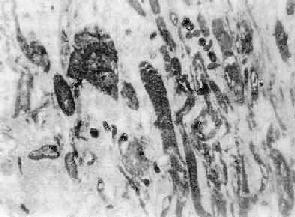

镜下,心肌梗死最常表现为凝固性坏死,心肌细胞胞浆嗜伊红性增高,继而核消失。肌原纤维结构可保持较长时间,最终融合成均质红染物(图8-31)。梗死灶边缘可见充血带及中性粒细胞浸润,在该处,可见到心肌细胞肿胀,胞浆内出现颗粒状物及不规则横带(图8-32)。另一部分心肌细胞则出现空泡变性,继而肌原纤维及细胞核溶解消失,残留心肌细胞肉膜,仿佛一个空的扩张的肉膜管子(图8-31)。

图8-31 心肌梗死

图左边示心肌纤维肿胀,横纹消失,伊红浓染,核溶解消失(凝固性坏死);右边心肌细胞原纤维及部分心肌核溶解消失(液化性肌溶解)